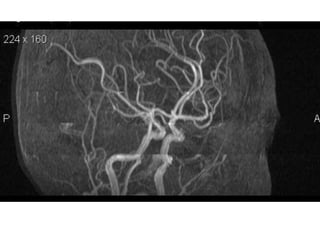

NORMAL MRA

Arteries of the brain (cranial view) - MRA

1. Anterior cerebral artery

2. Anterior communicating artery

3. Basilar artery

4. branches (in insula) of middle

cerebral artery

5. Cavernous portion of internal carotid

artery

6. Cervical portion of internal carotid

7. Genu of middle cerebral artery

8. Intracranial (supraclinoid) internal

carotid artery

9. Middle cerebral artery

10. Ophthalmic artery

11. Petrous portion of internal carotid

12. Posterior cerebral artery

13. Posterior cerebral artery in ambient

cistern

14. posterior cerebral artery in

interpeduncular cistern

15. Posterior communicating artery

16. Posterior inf cerebellar artery.

17. Quadrigeminal portion of posterior

18. Superior cerebellar artery

19. Vertebral artery